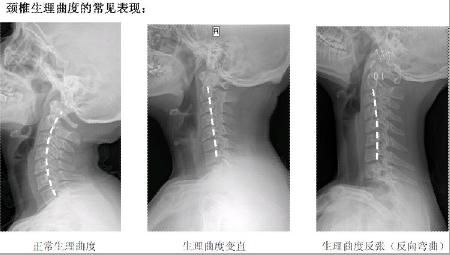

頸椎的病變過程

正常頸椎生理彎曲,可以使人呼吸通暢

從上面一組圖我們可以看出,頸椎正常的生理彎曲很重要。但現(xiàn)在,由于電腦的使用,很多人的頸椎都出現(xiàn)了不應(yīng)有的病變,頸曲度消失,甚至反張,會(huì)導(dǎo)致腦血出現(xiàn)障礙,引起包括頭暈、肩頸痛、手臂麻,以及頸心綜合癥等一系列問題,而昆叔正是由客戶的頸紋判定她的頸椎不好的。